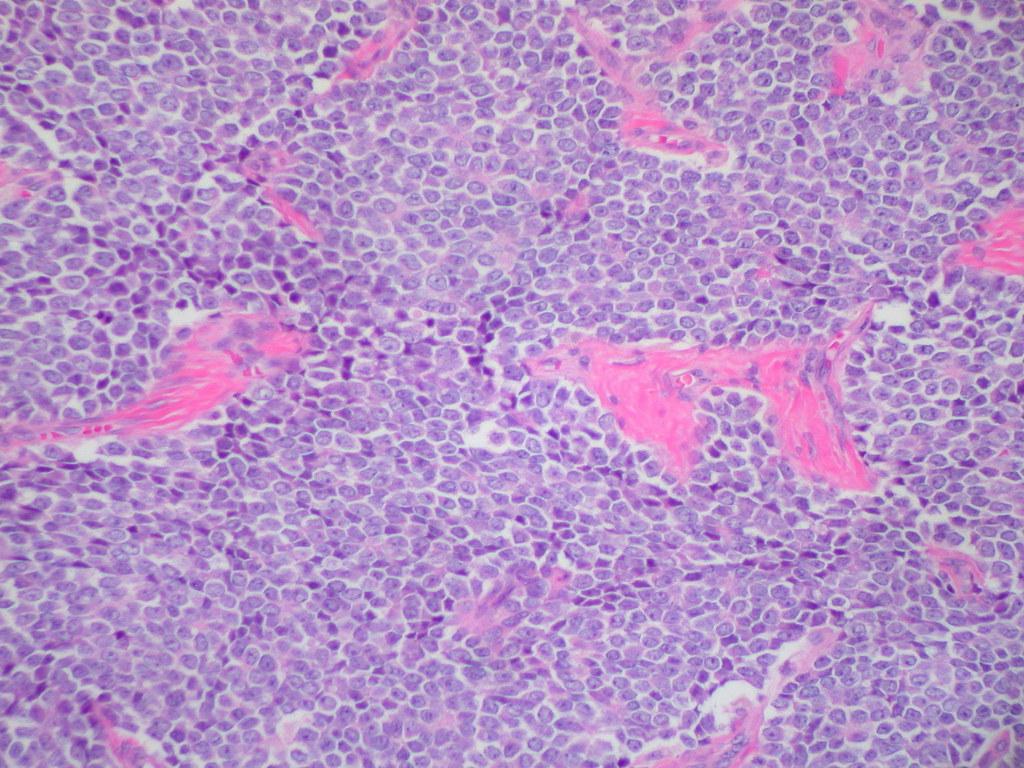

El sarcoma de Ewing es un tumor canceroso que se desarrolla en los huesos o en la parte del tejido que rodea los huesos, es decir, el tejido blando. Frecuentemente, crece en las piernas, las costillas, la pelvis, la columna vertebral o los brazos. También puede llegar a expandirse a los pulmones, la médula ósea y los huesos.

Como resultado, se produce una masa de células anormales (es decir, un tumor) con capacidad para invadir y destruir el tejido corporal sano. Estas células anormales pueden desprenderse e incluso propagarse (haciendo metástasis) por todo el cuerpo. En lo que respecta al sarcoma de Ewing, los cambios del ADN afectan con mayor frecuencia a un gen llamado EWSR1.